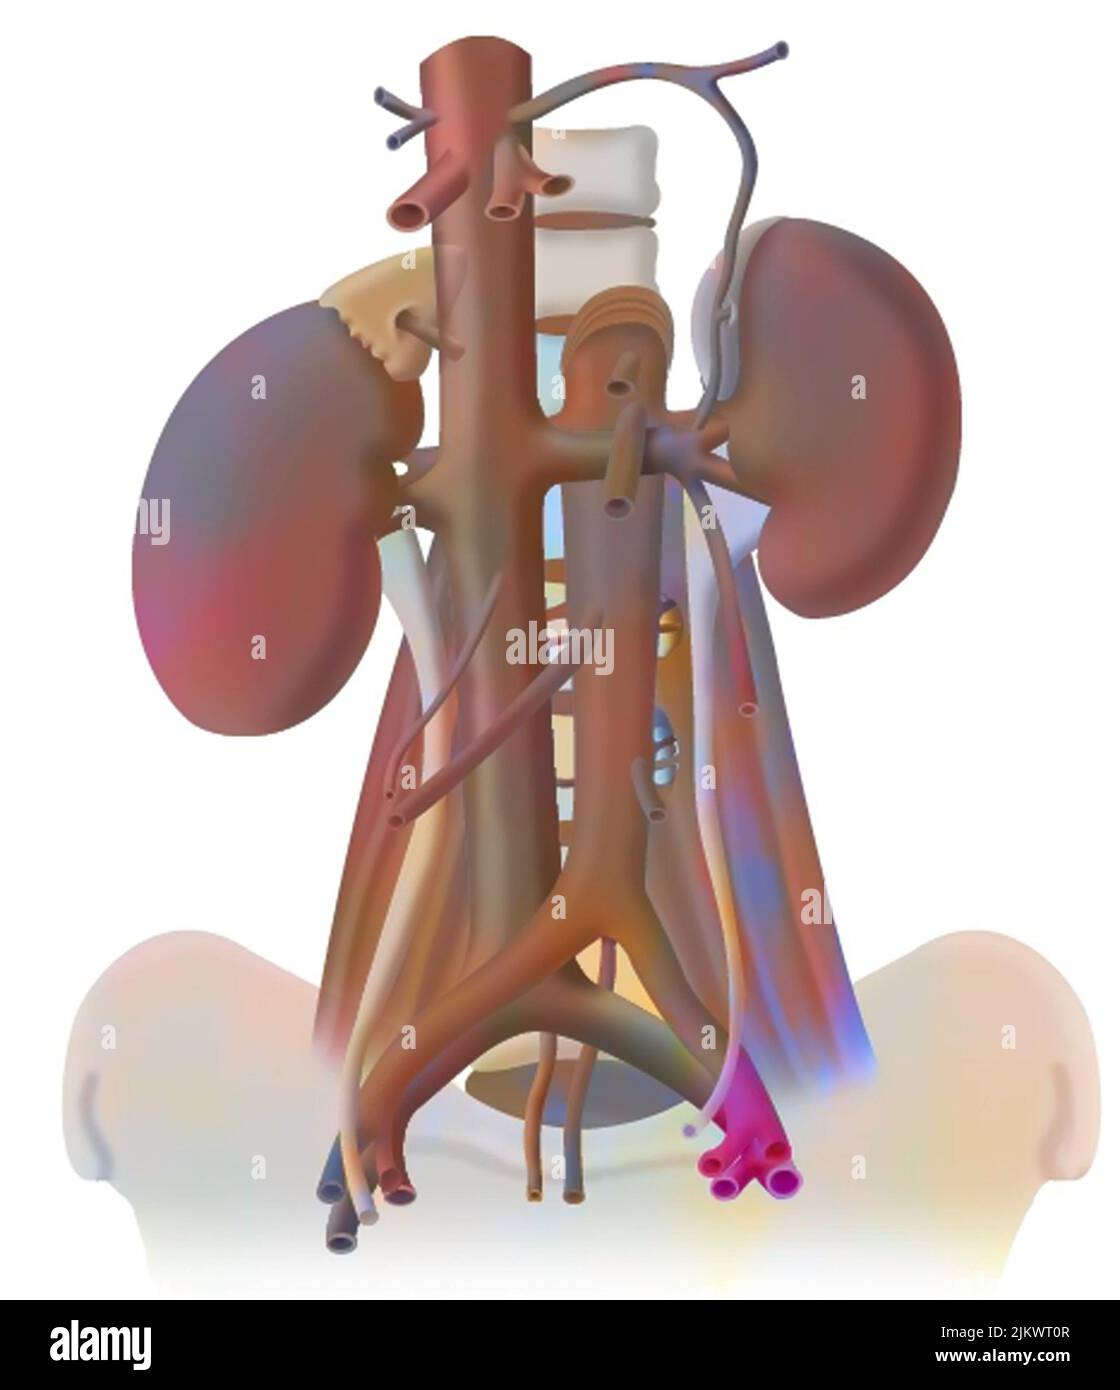

RF2X8JJJR–Die 3D-Darreichungsform von Krebs erfordert eine Blutversorgung, um die Nährstoffe und den Sauerstoff zu liefern, die sie zum Wachstum und Überleben benötigt

RF2X8JJJT–Die 3D-Darreichungsform von Krebs erfordert eine Blutversorgung, um die Nährstoffe und den Sauerstoff zu liefern, die sie zum Wachstum und Überleben benötigt

RF2X8JJJX–Die 3D-Darreichungsform von Krebs erfordert eine Blutversorgung, um die Nährstoffe und den Sauerstoff zu liefern, die sie zum Wachstum und Überleben benötigt